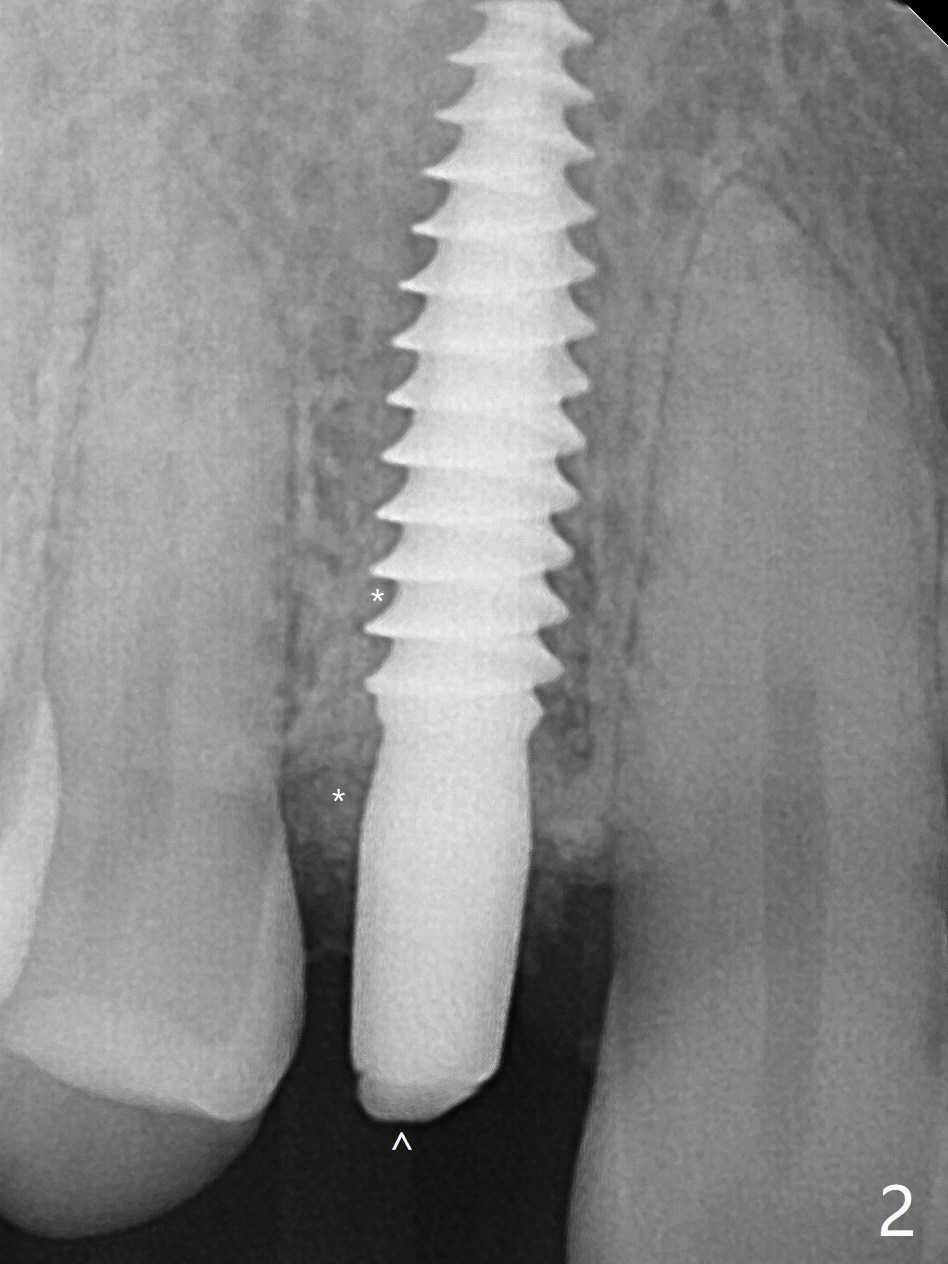

拔除根管治疗后第一双尖牙,花费不少时间(牙根松软,最后需要劈开),但是使用导板,植入一段式植体显得利索,不要花时间正确放置基台,而且植体冠部不仅没有与颊侧,舌侧骨板接触,而且与近中,远中牙槽嵴有一定空间(图一:*)对牙槽嵴没有压力,减少术后骨质吸收。降低基台高度后(图二:箭头),用骨粉充填(图二:*)。